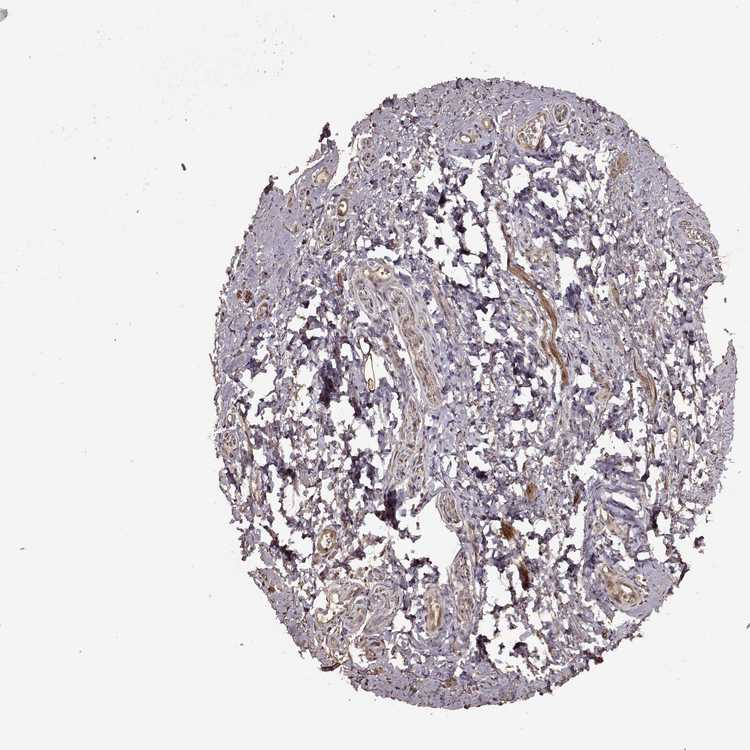

SOFT TISSUE 1 - Antibody stainingi

Antibody staining in the annotated cell types in the current human tissue is reported as not detected, low, medium, or high, based on conventional immunohistochemistry profiling in selected tissues. This score is based on the combination of the staining intensity and fraction of stained cells.

Each image is clickable and will lead to virtual microscopy that enables deeper exploration of all samples and also displays staining intensity scores, fraction scores and subcellular localization as well as patient and tissue information for each sample.

Antibody HPA072204

Chondrocytes Medium

Fibroblasts Low

Peripheral nerve High